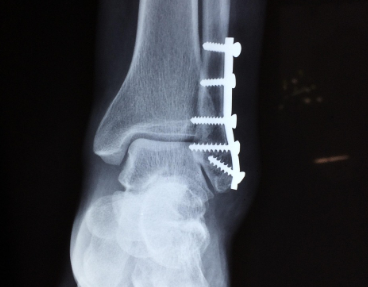

병원에서는 손상 정도를 확인하기 위해 X-ray, 초음파, MRI 검사를 진행합니다. 골절이 동반되지 않았더라도, 인대의 완전 파열 여부를 확인해야 치료 방법이 달라집니다.

- 수술적 치료 (완전 파열)

- 끊어진 인대를 봉합하거나, 필요 시 재건술 시행

- 수술 후 약 6주 이상 고정

- 이후 물리치료와 균형·근력 회복 훈련을 통해 점진적으로 보행 회복